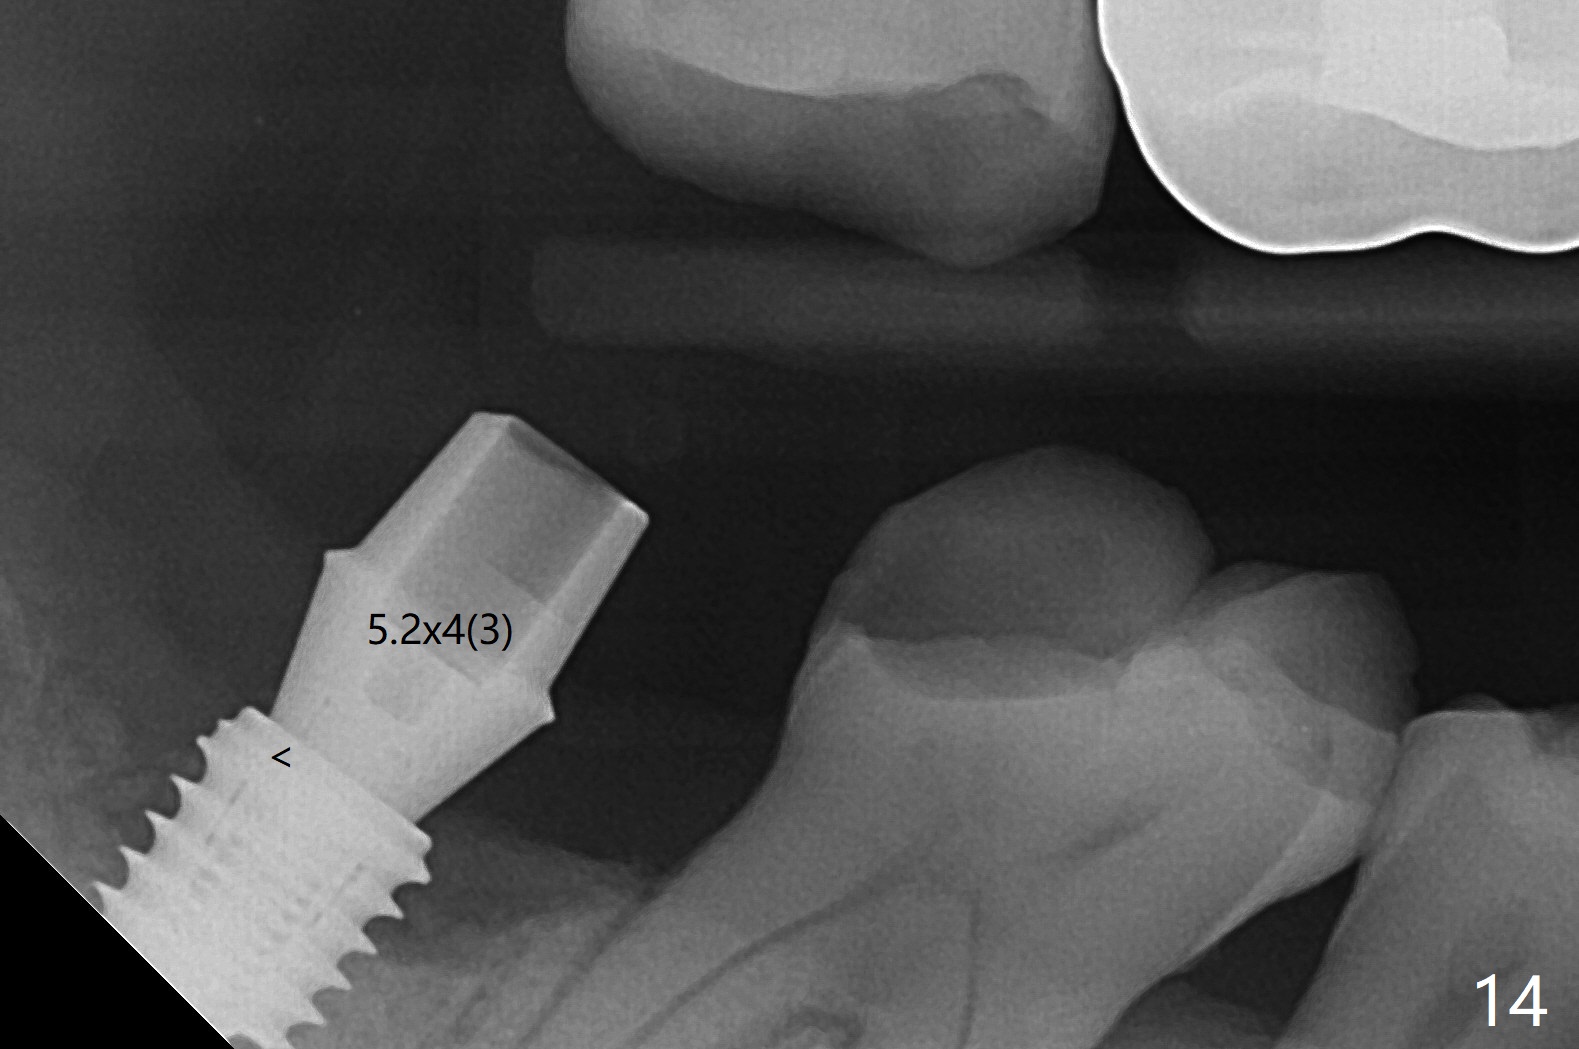

The residual roots of the tooth #31 are lower buccal (Fig.1 B), which in fact is molded and worn by the supraerupted tooth #2. When the tooth is extracted (Fig.2) and an implant, abutment (Fig.3 gold colored) and allograft (*) are placed, the abutment has to be trimmed. An atypical immediate provisional is fabricated by spreading setting acrylic over the abutment and bone graft (Fig.4 P) with occlusal equilibrium. Advantages of the guided surgery are good position (Fig.3 buccolingual), trajectory and depth (Fig.5,6) of the implant. The buccodistally exposed implant threads are packed with allograft in sufficient amount (Fig.3,5,6 *). The atypical immediate provisional breaks down and dislodges 3 weeks postop (Fig.7). In fact the implant plateau is exposed buccally. A monojet is given to the patient for self cleansing. He is instructed to return in 3 weeks. The exposed implant threads are covered 1.5 months postop (Fig.8). Incomplete abutment seating (Fig.9 <) was not noted until 1 year 3 month post cementation when the crown was mobile (Fig.10). A 6x3 mm healing abutment is placed. Three days later, the crown is sectioned and separated from the abutment. The latter returns to place; due to angulation associated with PA, the gap between the implant and abutment is indistinct (Fig.11). Bitewing is taken; the gap exists (Fig.12 <). The abutment seems to be seated deep; there is apparently soft tissue interference. A 5.2x4(2) mm abutment remains incompletely seated (Fig.13 >). A 5.2x4(3) mm one is completely seated (Fig.14 <). Zirconium crown with an access hole is cemented in the mouth. The crown and abutment is then removed for residual cement removal and reseated and torqued (Fig.15). Four months later, the Zirconium crown is fractured (Fig.16). Impression is retaken for high noble metal crown without access hole for strength (Fig.17).